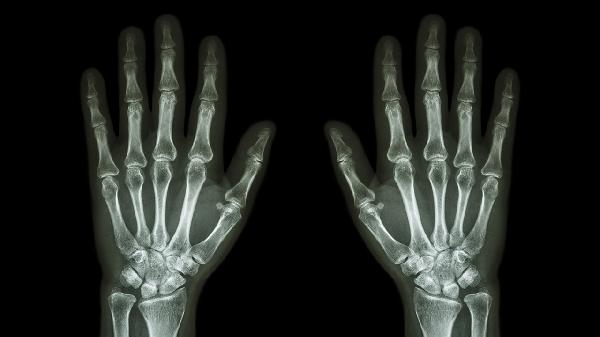

关节软骨磨损导致骨面直接摩擦产生粗糙响声,多见于中老年人。可能伴随关节肿胀和晨起僵硬。建议控制体重减少关节负荷,医生可能推荐硫酸氨基葡萄糖胶囊、塞来昔布胶囊等药物。

日常应注意避免拇指过度用力或重复性动作,使用电子设备时每隔30分钟活动手指。出现持续疼痛、关节变形或活动受限时应及时就诊骨科或风湿免疫科,通过X线、超声等检查明确诊断。寒冷季节注意手部保暖,可适当热敷促进血液循环。